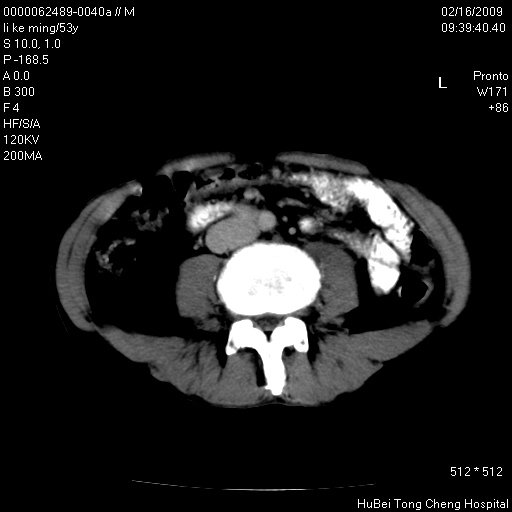

以下是引用卜一在2009-2-16 16:13:00的发言:[br]胰胆管扩张,末端明显狭窄 梗阻,胰头及十二指降段壶腹部结构紊乱。多考虑:十二指降段壶腹部癌!

以下是引用zsl6918在2009-2-17 8:48:00的发言:[br]符合胰头癌侵犯十二指肠。